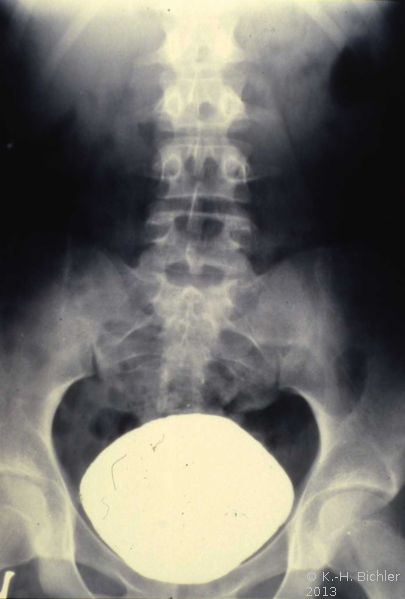

Die ausgedehnte retroperitoneale LK-Metastasierung (Bulky disease) eines Hodentumors (Embryonalkarzinom und Seminom) mit Ummauerung der großen Gefäße (Aorta und Vena cava) sowie des linksseitigen Nierengefäßstieles führte bei dem jungen Mann zu einer vasculär bedingten Schrumpfung der linken Niere (Abbildung 18a,e) (

s. Tumoren/Hoden).

In der Sonographie fand sich eine kleine Niere links bei unauffälliger rechter Niere (Abbildung 18b).